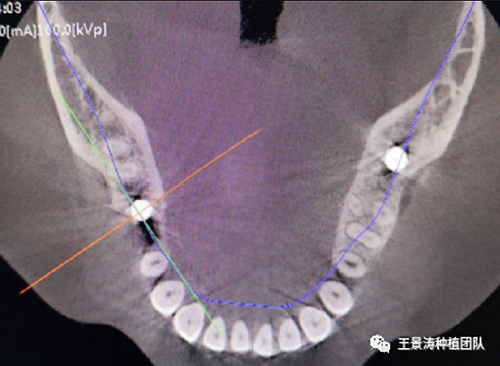

其次初期穩(wěn)定性的獲得,前牙美學(xué)區(qū)種植體的初期穩(wěn)定性主要是依靠腭舌側(cè)骨板及基底骨來獲得的。后牙區(qū)的穩(wěn)定性主要依靠多根牙的牙槽間隔及根尖到重要解剖位置的高度的骨質(zhì)獲得(主要是竇嵴距和管嵴矩的高度,還要參考植入種植體的長度),因此術(shù)前仔細(xì)測量牙槽間隔與根尖至重要解剖結(jié)構(gòu)的高度是后牙即刻種植的關(guān)鍵因素之一。

左側(cè)下頜第二磨牙及右側(cè)下頜第一磨牙同時即刻種植病例。患者年輕女性,無系統(tǒng)性疾病。37及46殘冠及殘根,且46劈裂,無法冠修復(fù),必須拔除。37根尖慢性炎癥,大量肉芽組織存在,46根分叉較高,根分叉骨質(zhì)尚可。CBCT示:根尖骨質(zhì)至下牙槽神經(jīng)管距離可滿足種植體的初期穩(wěn)定性,遂考慮即刻種植,并在種植體周邊填入骨粉并覆蓋骨膜,雙側(cè)的種植體初期穩(wěn)定性相差無幾,但考慮到37根尖慢性炎癥較大,遂給予埋入式種植。